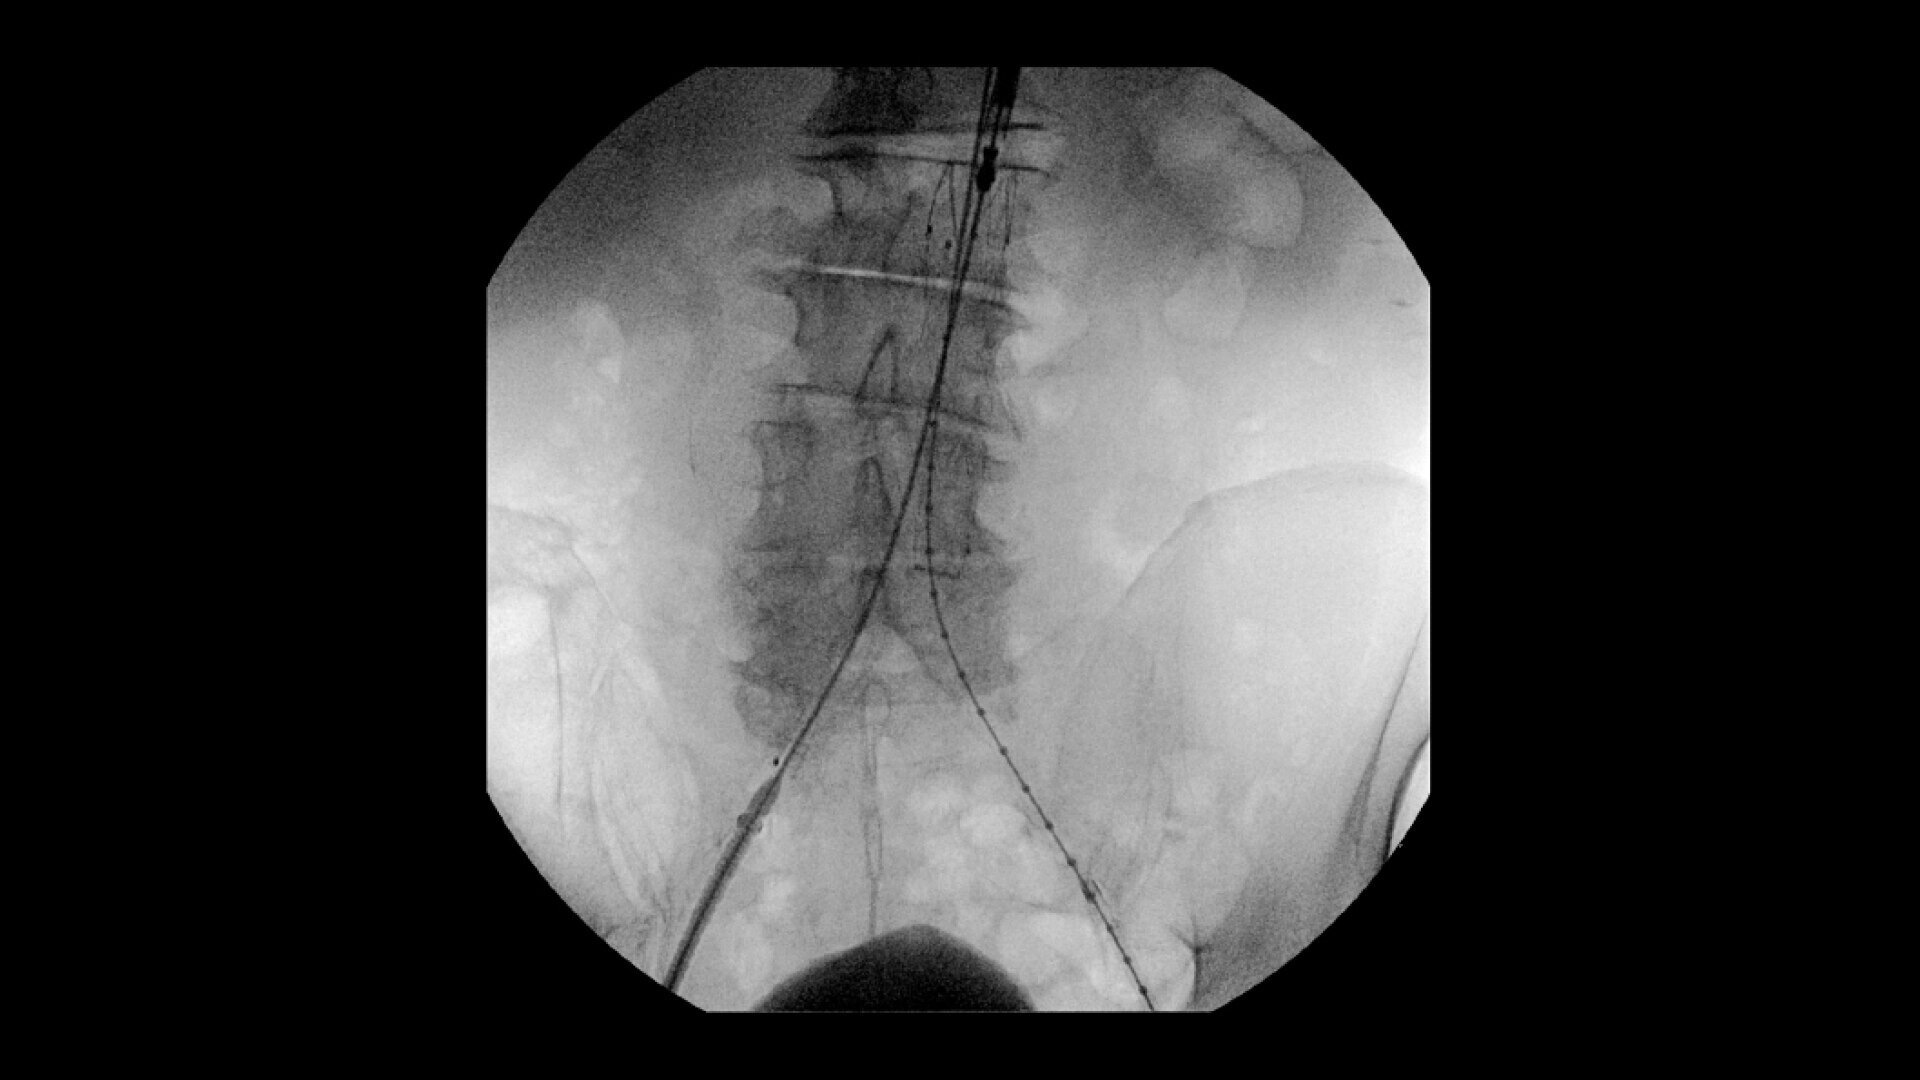

Complex vascular procedures require powerful imaging systems. OEC premium C-arms perform in a variety of procedures such as:

• Recanalization and stent placement in iliac arteries

• Vascular long lesion treatment